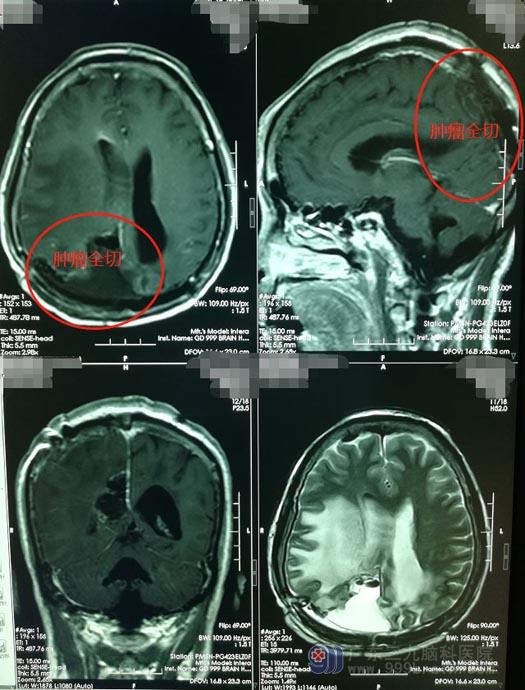

第三次手术,对手术医生的技术要求很高,医院副院长、神经外五科主任鲁明带领团队,凭着扎实的手术功底及多年的成功经验决定迎着困难上,在全麻下为钟姨行右顶枕镰窦复发脑膜瘤切除术。术中见上失状窦顶枕部闭塞,肿瘤起源于顶枕部大脑镰,主体位于右顶枕部,小部分肿瘤自大脑镰突入左侧枕部,肿瘤深部长入右侧脑室角,部分肿瘤侵入脑实质,右侧脑室角破损,予以修补、肿瘤全部切除;顶枕部受肿瘤侵袭的部分大脑镰以及长入上失状窦内的肿瘤也予以切除,闭塞的上失状窦前后段均予以妥善结扎。手术过程顺利,术中无重要血管及主要静脉窦损伤。

术后第2天,钟姨即转回普通病房,右侧肢体肌力正常,胃口也不错,左侧肢体肌力因为拖延比较久受影响,术后还需要行康复治疗慢慢恢复。